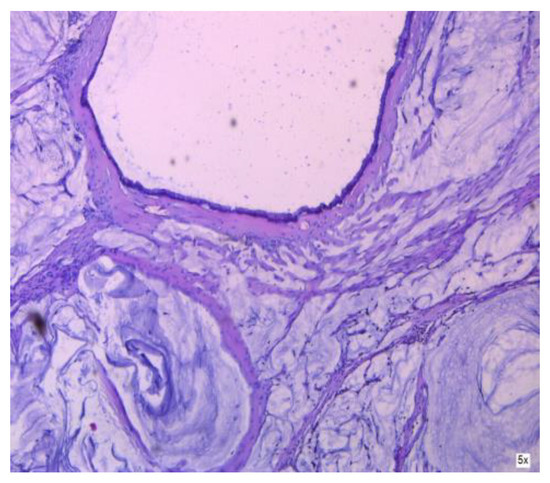

3.1.1. Mucinous Cystadenoma